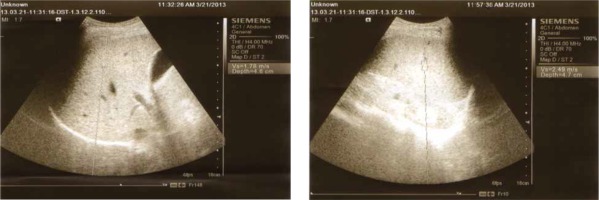

Abdominal ultrasound was performed in all participants to assess the liver and spleen size and determine PPT. All subjects underwent ARFI elastography using a Siemens Acuson S3000 Virtual Touch ultrasound system (Siemens AG, Erlangen, Germany) employing a 4CI transducer. The shear waves generated by the acoustic pulse propagates into the tissue and is directed to the side of a region of interest (ROI); their speed is measured in meters per second. The examination was carried out by the intercostal approach in the right liver lobe, 1-2 cm under the liver capsule; while the patient was fasting, in the supine position and with the right arm fully abducted. The patient was asked to hold the breath for a moment. The mean of 8-10 valid measurements was determined (Fig. 1). All participants were assessed by the same operator who conducted the sonographic and ARFI screening to avoid inter-observer variability.